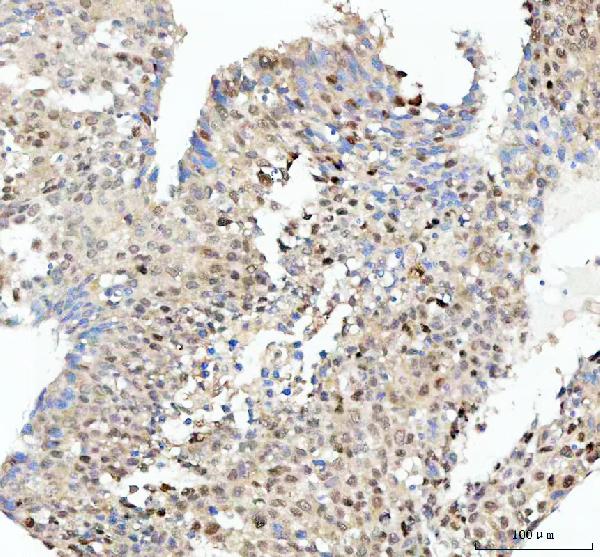

Figure 2. IHC analysis of SOX9 using anti-SOX9 antibody (M00177). SOX9 was detected in a paraffin-embedded section of human colorectal adenocarcinoma tissue. Heat mediated antigen retrieval was performed in EDTA buffer (pH 8.0, epitope retrieval solution). The tissue section was blocked with 10% goat serum. The tissue section was then incubated with 1:50 rabbit anti-SOX9 Antibody (M00177) overnight at 4°C. Peroxidase Conjugated Goat Anti-rabbit IgG was used as secondary antibody and incubated for 30 minutes at 37°C. The tissue section was developed using HRP Conjugated Rabbit IgG Super Vision Assay Kit (Catalog # SV0002) with DAB as the chromogen.